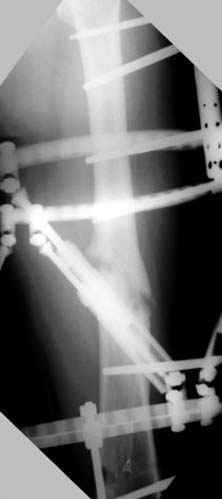

Djoldas Kuldjanov 23 Ноябрь 2004, 18:21

пластическая модель; и коррекция бедра аппаратом Илизарова.

Имею другие снимки тоже, получится как отчет о моей работе.

хотя даже если бы и инфекция , то nail exchange с рассверливанием канала - вариант дебрайдмента) Я думаю, что последовательность развития событий:

Узкий к-м канал - тонкий гвоздь- усталостный перелом дистальных винтов - развитие нестабильности и как ее результат остеолиз вокруг гвоздя - деформация анатомической оси бедра. Похоже, что я понял почему аппарат, а не новый гвоздь:-)